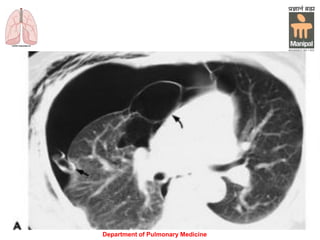

Computed tomography: Bilateral pleural effusions

are present as a result of pneumonia

Computed tomography: Bilateralpleural effusions are present as a result of pneumonia Department of Pulmonary Medicine